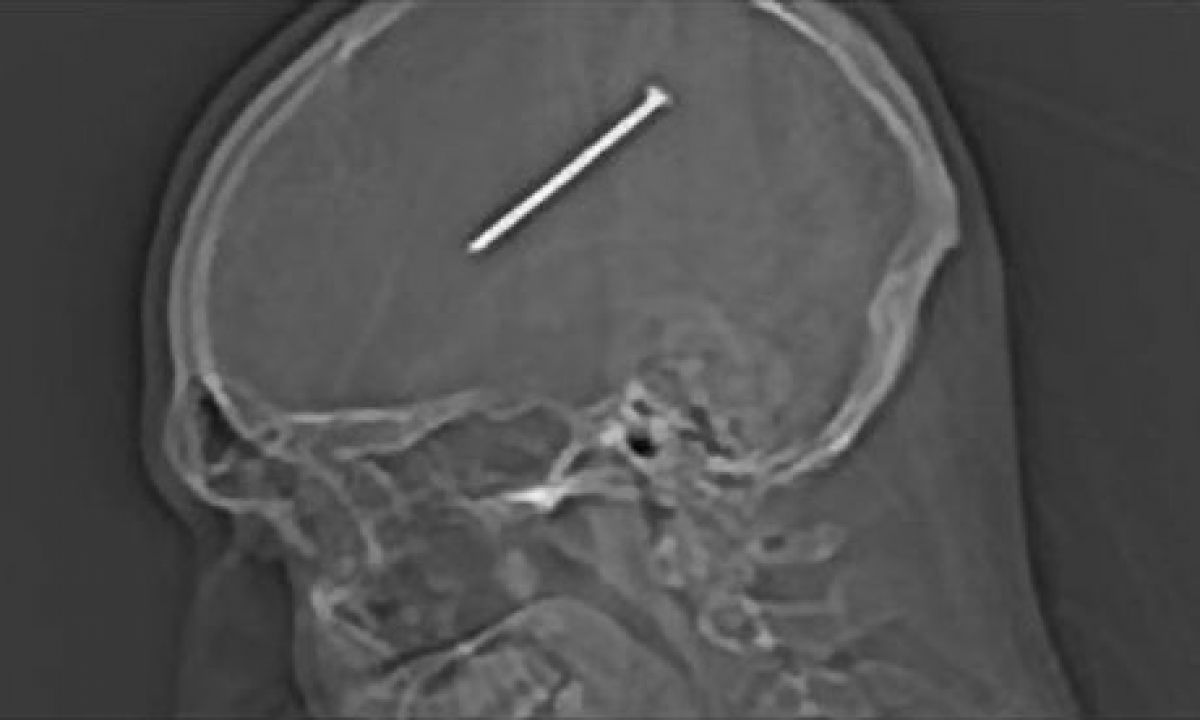

Am scris câteva strofe și despre fiica mea și tatăl meu, dar și despre moartea lui Michael Jackson. Am făcut referire și la corupția din justiție. Nu îmi fac ciorne înainte, ci totul vine de la sine”, povestea Florin Geanopol, din Penitenciarul Iași.  Incă din acea perioadă, suceveanul a făcut unele demersuri la conducerea închisorii ieșene, dorind să-și omologheze lucrarea drept „cea mai lungă poezie din lume”. Cei de la Guiness World Records i-au promis lui Geanopol că vor trimite o echipă la Vatra Dornei pentru a-i omologa poezia. In perioada în care a stat închis, individul a încercat să doboare un alt record mondial. Când se afla încarcerat la Penitenciarul Botoșani, ca semn de protest, pentru că nu a fost lăsat de conducere să participe la înmormântarea tatălui său, Florin Geanopol și-a bătut un cui în cap, cu care a stat așa timp de nouă luni, recordul mondial fiind de șapte luni. Pe lângă cele două închisori din Moldova, Geanopol a „frecventat” și Penitenciarul Rahova. După eliberare, suceveanul a dat în judecată statul român pentru condițiile insalubre de la închisoarea Rahova, iar cei de la CEDO i-au dat dreptate, obligând statul român să-i plătească despăgubiri în valoare de 3.000 de euro.

VEZI ȘI: Deţinut cu un cui în cap, gata de “Cartea Recordurilor” pentru Eminescu